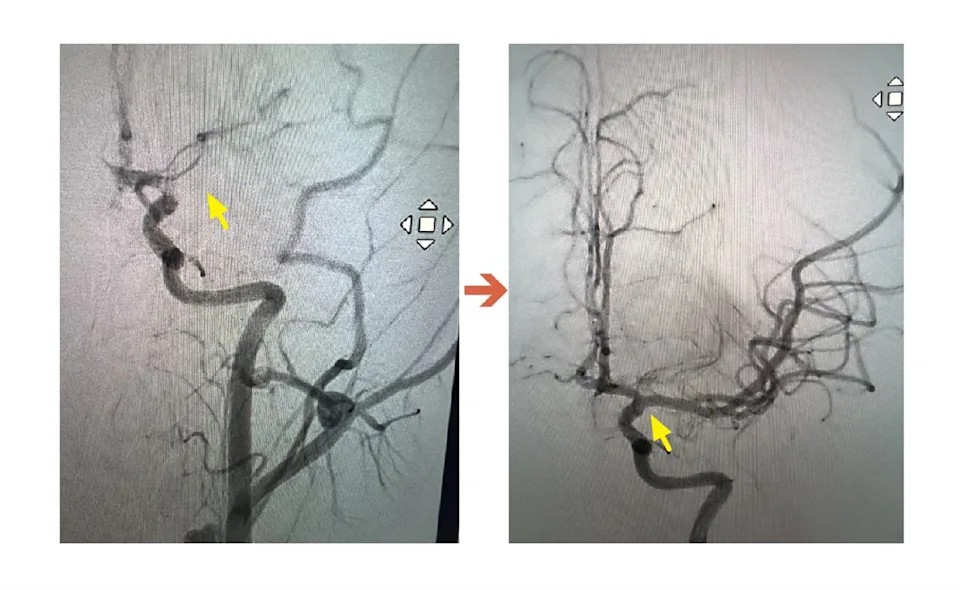

從ICA血管攝影可見,圖左箭頭處為血栓阻塞血管,圖右箭頭處則是已打通的血管。聯新國際醫院提供

檢查結果出爐後,神經內科李振華醫師迅速判讀,確認為左側中大腦動脈栓塞造成的缺血性腦中風。經和家屬充分溝通後,影像醫學科主任暨取栓醫師郭葉璘隨即和團隊進行急性腦中風顱內動脈血栓移除,並從腹股溝導引導管至左側中大腦動脈阻塞處,採用強力抽吸方式清除血栓,從手術開始到打通血管,全程僅花費約10分鐘,就成功取出4個血栓,最大達1.1公分。